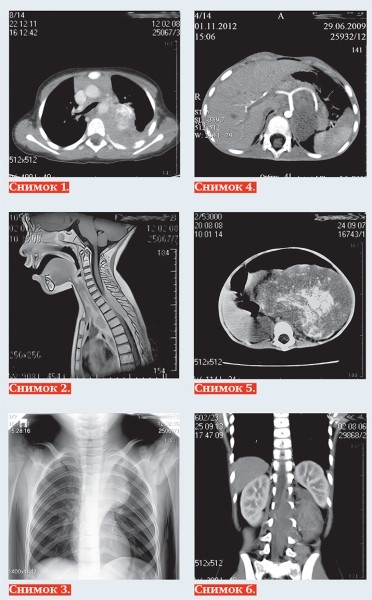

• Нейробластома у детей: пути снижения запущенных случаев